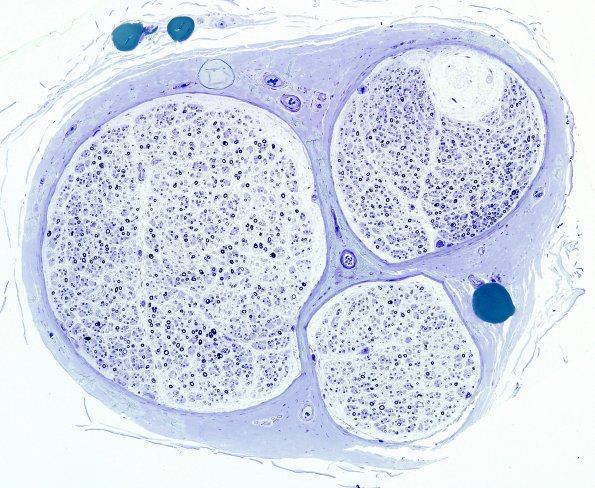

This low magnification image shows significant loss of large and small myelinated axons. The upper right fascicle contains a Renaut body. (plastic sections).